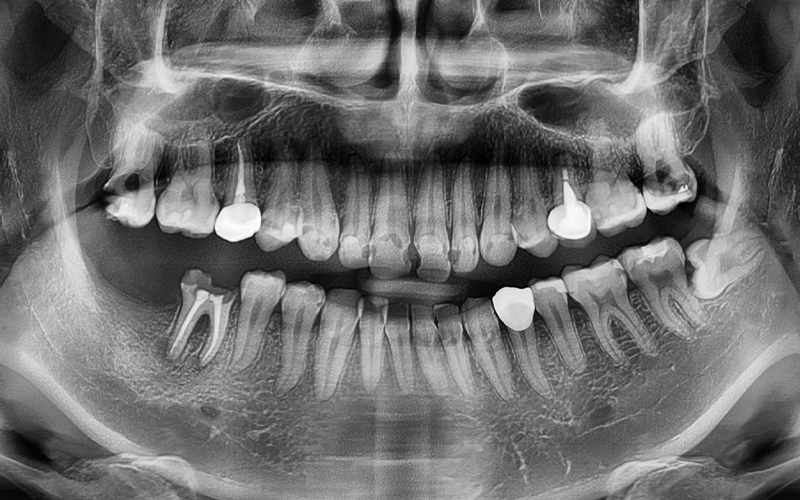

파노라마 사진을 촬영해

정밀 체크를 진행하였고,

전체적인 치료를 계획하였습니다.

파노라마상에서도 성공적으로

치료가 진행 된 모습을 체크하실 수 있습니다.

현재 임플란트는

인공치근 부분인

픽스처만 식립되어 있는 상태로,

추후 크라운(보철물)을 올리는

보철과정까지 잘 마무리 해드리기로 했습니다.